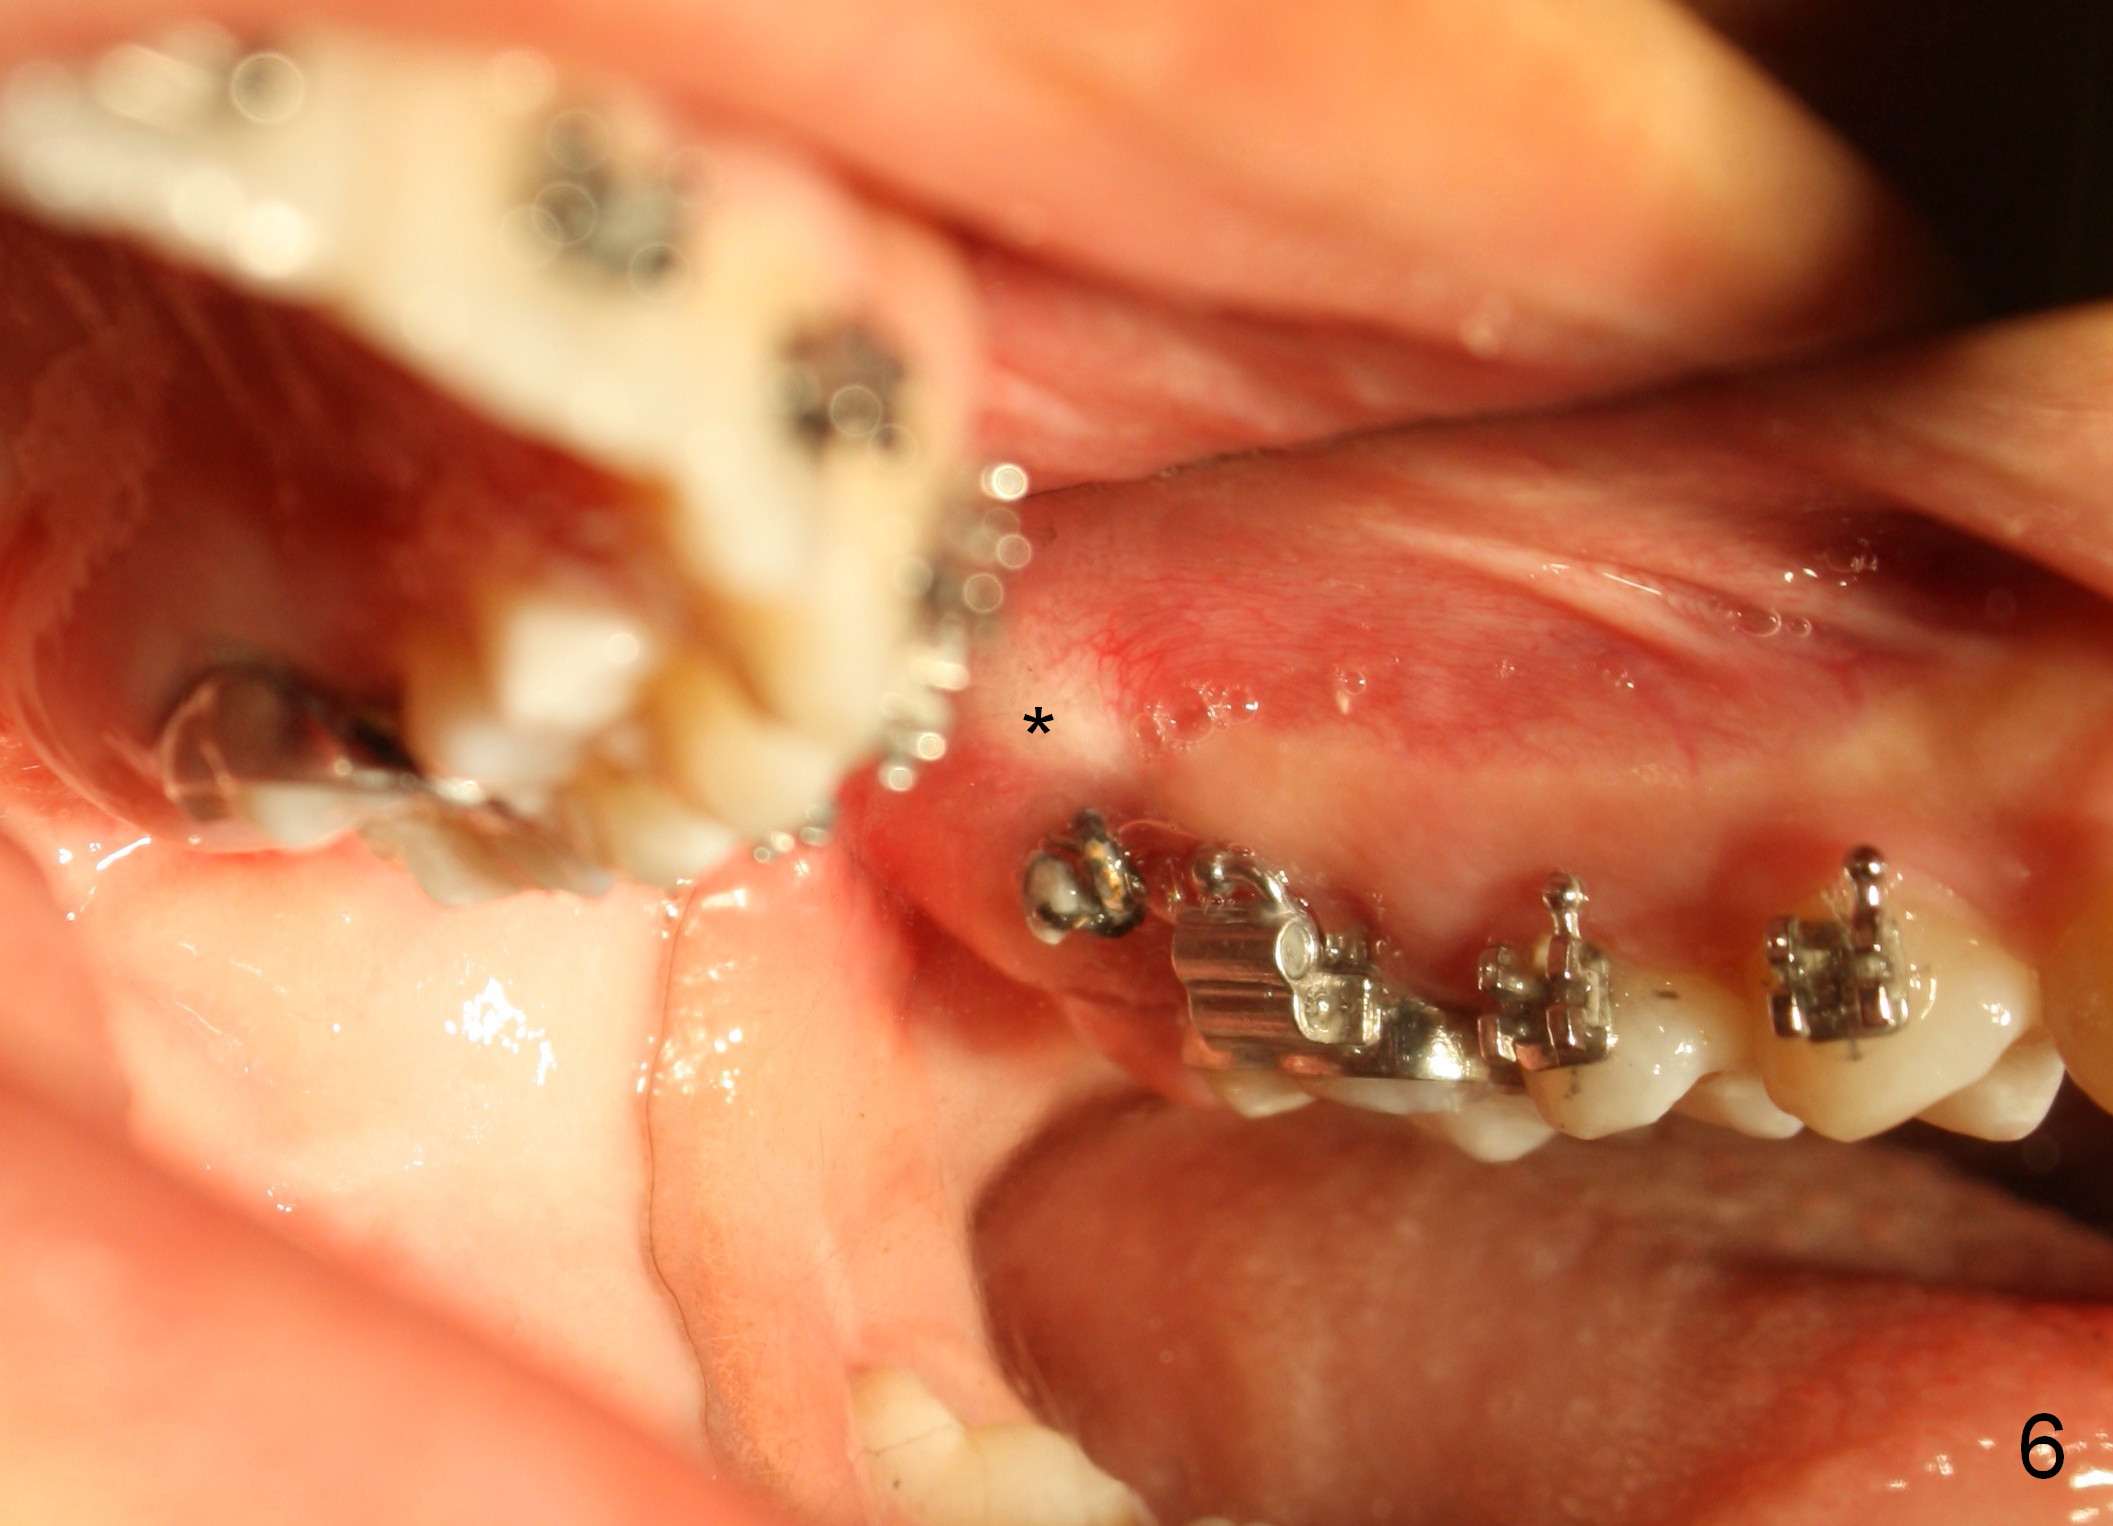

The distobuccal cusp of the tooth is subgingival 8 months post banding (Fig.6 (mirror view) *). A 2nd surgery is performed to expose the gold chain (Fig.7 <) and a bracket is placed. With arch wires, eruption of the impacted tooth is quickened (Fig.8). Later a 3rd minor surgery is done to place a lingual button to facilitate lingual cusp eruption. Finally a band has to be placed at #15. Treatment finishes in 2 years. The patient (15 years 2 months old) returns for follow up 3 months post debanding (Fig.9). There is no bone loss around the tooth #15 2 years 4 months post de-banding (Fig.11, as compared to the tooth #2 (Fig.10)).